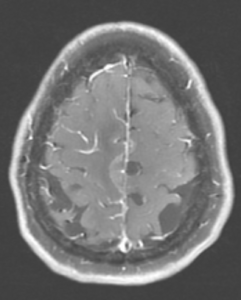

Figure 1A: T2/FLAIR sequence demonstrating right greater than left parasagittal frontal and parietal cortical T2/FLAIR hyperintensity and edema with involvement of the subcortical and deep white matter. There is also incomplete FLAIR suppression of the cerebrospinal fluid in the adjacent sulci, indicative of an inflammatory process. (Click to enlarge.)

Magnetic resonance imaging (MRI) of her brain revealed a right parasagittal T2/FLAIR, and cortical and subcortical white matter hyperintensity with gyral enhancement concerning for primary or metastatic malignant disease.